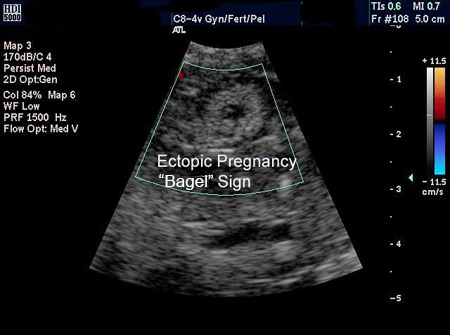

Un embarazo ectópico se visualiza en la ecografía transvaginal (ETV) y el diagnóstico se realiza directamente.[Figure caption and citation for the preceding image starts]: Imagen de ecografía de un embarazo ectópico que muestra el signo de la forma de "rosquilla"De la colección de la Dra. Melissa Fries; usado con permiso [Citation ends].

[Figure caption and citation for the preceding image starts]: Imagen de ecografía de un embarazo ectópico que muestra el signo de la forma de "rosquilla"De la colección de la Dra. Melissa Fries; usado con permiso [Citation ends].

Una masa anexial que se desplaza separada del ovario, a veces denominada "signo del deslizamiento", con un saco gestacional vacío a veces descrito como "anillo tubárico" o "signo del bagel" y una masa anexial compleja, no homogénea, que se desplaza separada del ovario, son altamente sugestivos de un embarazo ectópico, pero no son diagnósticos.[62]